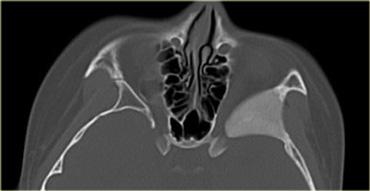

Ở trẻ em, vôi hóa trong nhãn cầu được coi là u nguyên bào võng mạc (retinoblastoma) cho đến khi được chứng minh ngược lại, kể cả khi tổn thương xuất hiện hai bên.

Hình bên trái là hình ảnh của một thiếu niên bị u nguyên bào võng mạc hai bên.

Hình bên trái là hình ảnh của một bé gái 13 tháng tuổi với các tổn thương hai bên do u nguyên bào võng mạc hai bên.

Hình bên trái là hình ảnh của một bệnh nhân khác bị u nguyên bào võng mạc.

Khối u này biểu hiện dưới dạng một vôi hóa lớn.

Khi u nguyên bào võng mạc chiếm hơn một nửa nhãn cầu, như trong trường hợp này, nhãn cầu phải được khoét bỏ.